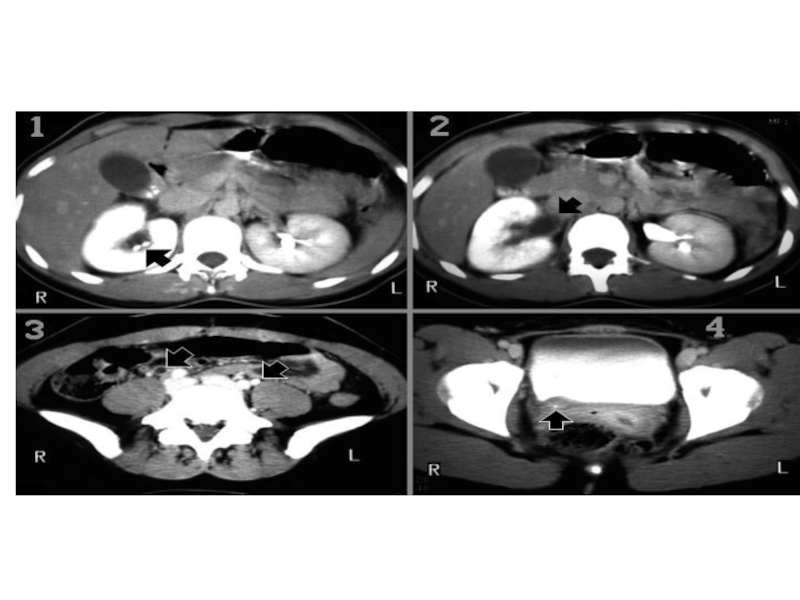

Слайд 1161- визуализируются камни в правой почке

2,3- диллатирована правая уретра

4- стрелка указывает

на камень в правой уретре

У пациента диагностированы пиелонефрит, уретерогидронефроз, уролитиаз